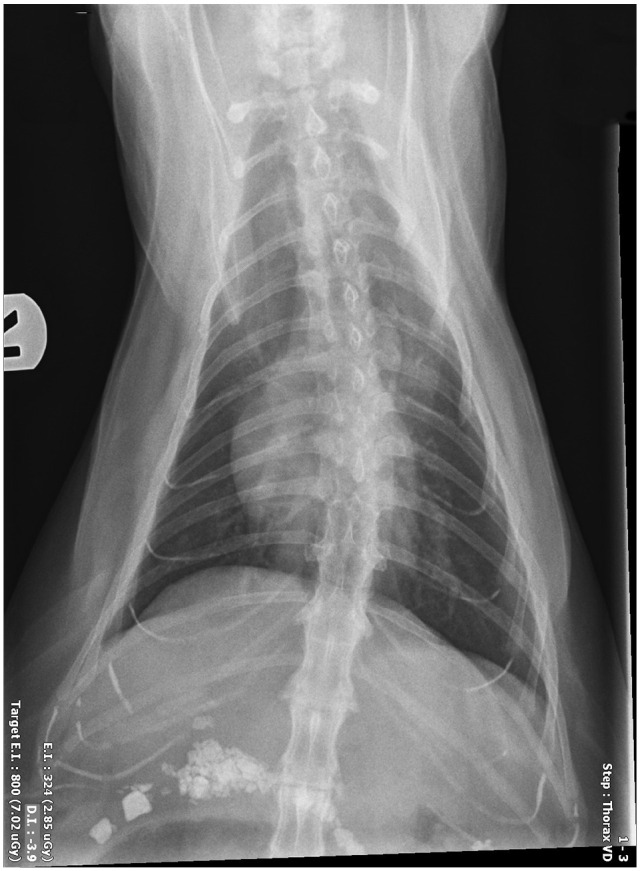

Case summary: A 7-year-old castrated male domestic shorthair cat was presented for surgical intervention for obstructive pancreatolithiasis. The patient had a history of chronic weight loss, vomiting and lethargy. Elevation of feline pancreas-specific lipase and a marked decrease in cobalamin were documented on blood biochemistry. Abdominal ultrasound revealed an enlarged right pancreatic limb with a dilated central duct and multiple pancreatoliths visualized within, consistent with partial pancreatic duct obstruction. The patient was successfully treated with a minor duodenal papilla construction using a 2.5 Fr double pigtail ureteral stent.

Relevance and novel information: Pancreatolithiasis is an exceptionally rare condition in veterinary medicine, particularly in cats, with only a few reported cases. Given its low incidence, there is no established consensus regarding the best therapeutic options in clinical practice. This case report outlines the successful application of a locking loop catheter to re-establish the patency of a pancreatic duct. Notably, this is the first documented use of this technique for the surgical management of obstructive pancreatolithiasis.